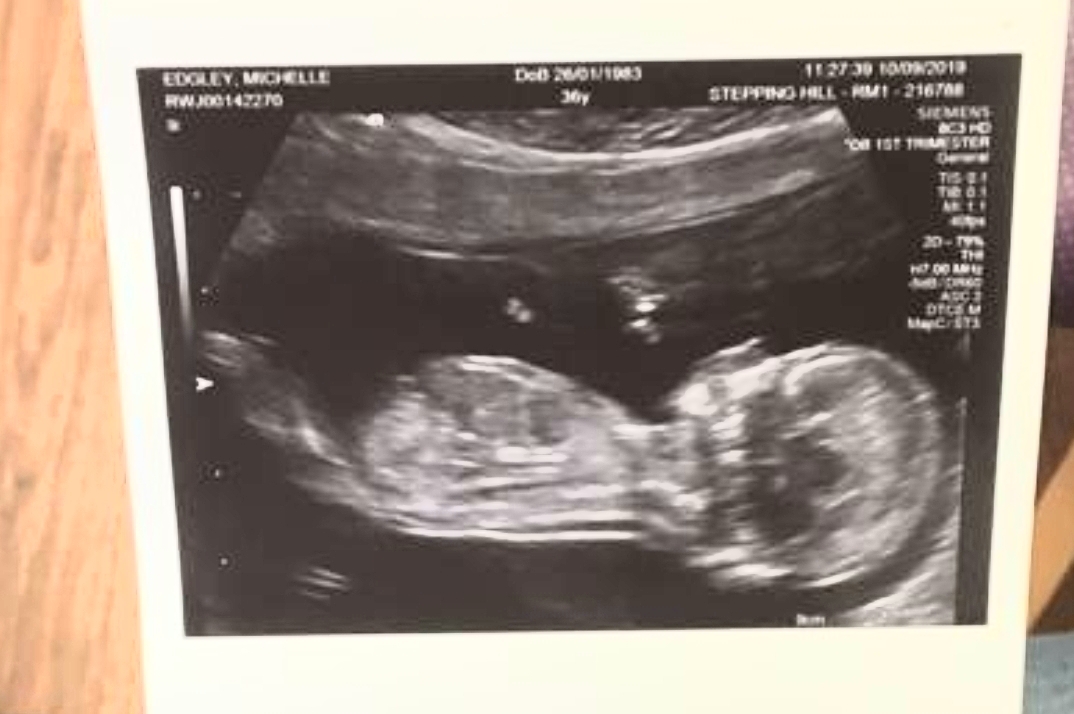

Not the best pics from scan but baby is 12 weeks 6 days.

It's our first baby and so excited!

The third pic baby is upside down